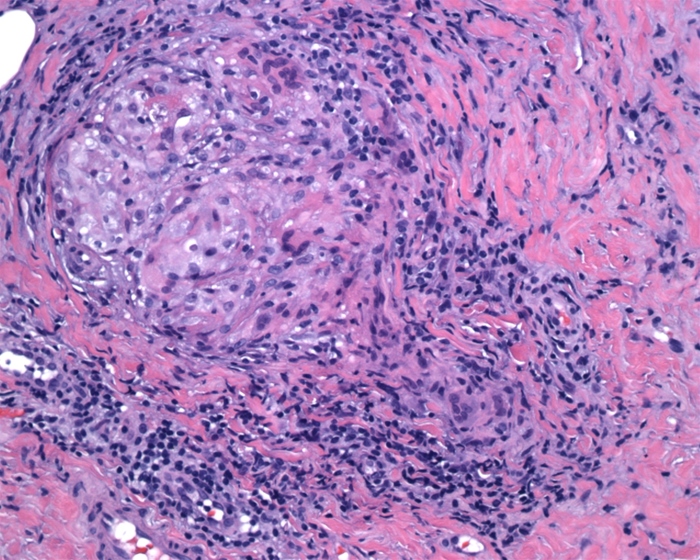

A 29-year-old African American woman is being evaluated for exertional dyspnea and dry cough. She has no significant medical history and takes no medications. The patient works part-time as a bird keeper at a zoo. She smokes 4 packs daily. CT-guided lung biopsy is performed; findings are shown in the image below.

This patient most likely has which of the following conditions?